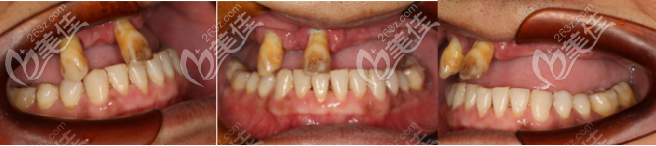

(术前牙齿状况)

(术后效果)